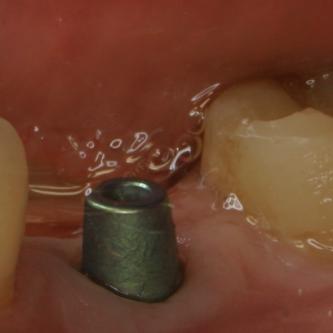

Exemple 11: Après cicatrisation environ 6 mois, le moignon est vissé sur l'implant.

Exemple 12: Les moignons vissés sur les implants 6 mois plus tard.